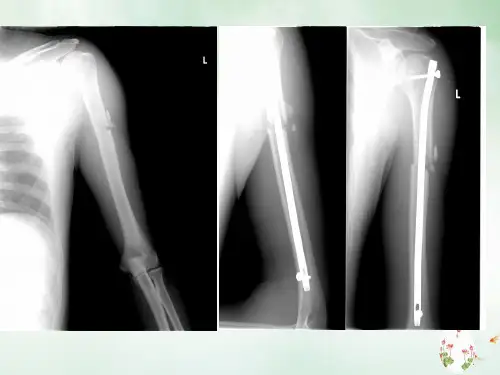

股骨干骨折

股骨干骨折是指转子下、股骨髁上的这一段骨干的骨 折。

重物直接打击、车轮辗轧、火器性损伤等直接暴力作 用于股骨,容易引起股骨干的横形或粉碎性骨折,同时有 广泛软组织损伤。股骨干骨折可以分为上1/3、中1/3和下 1/3骨折。